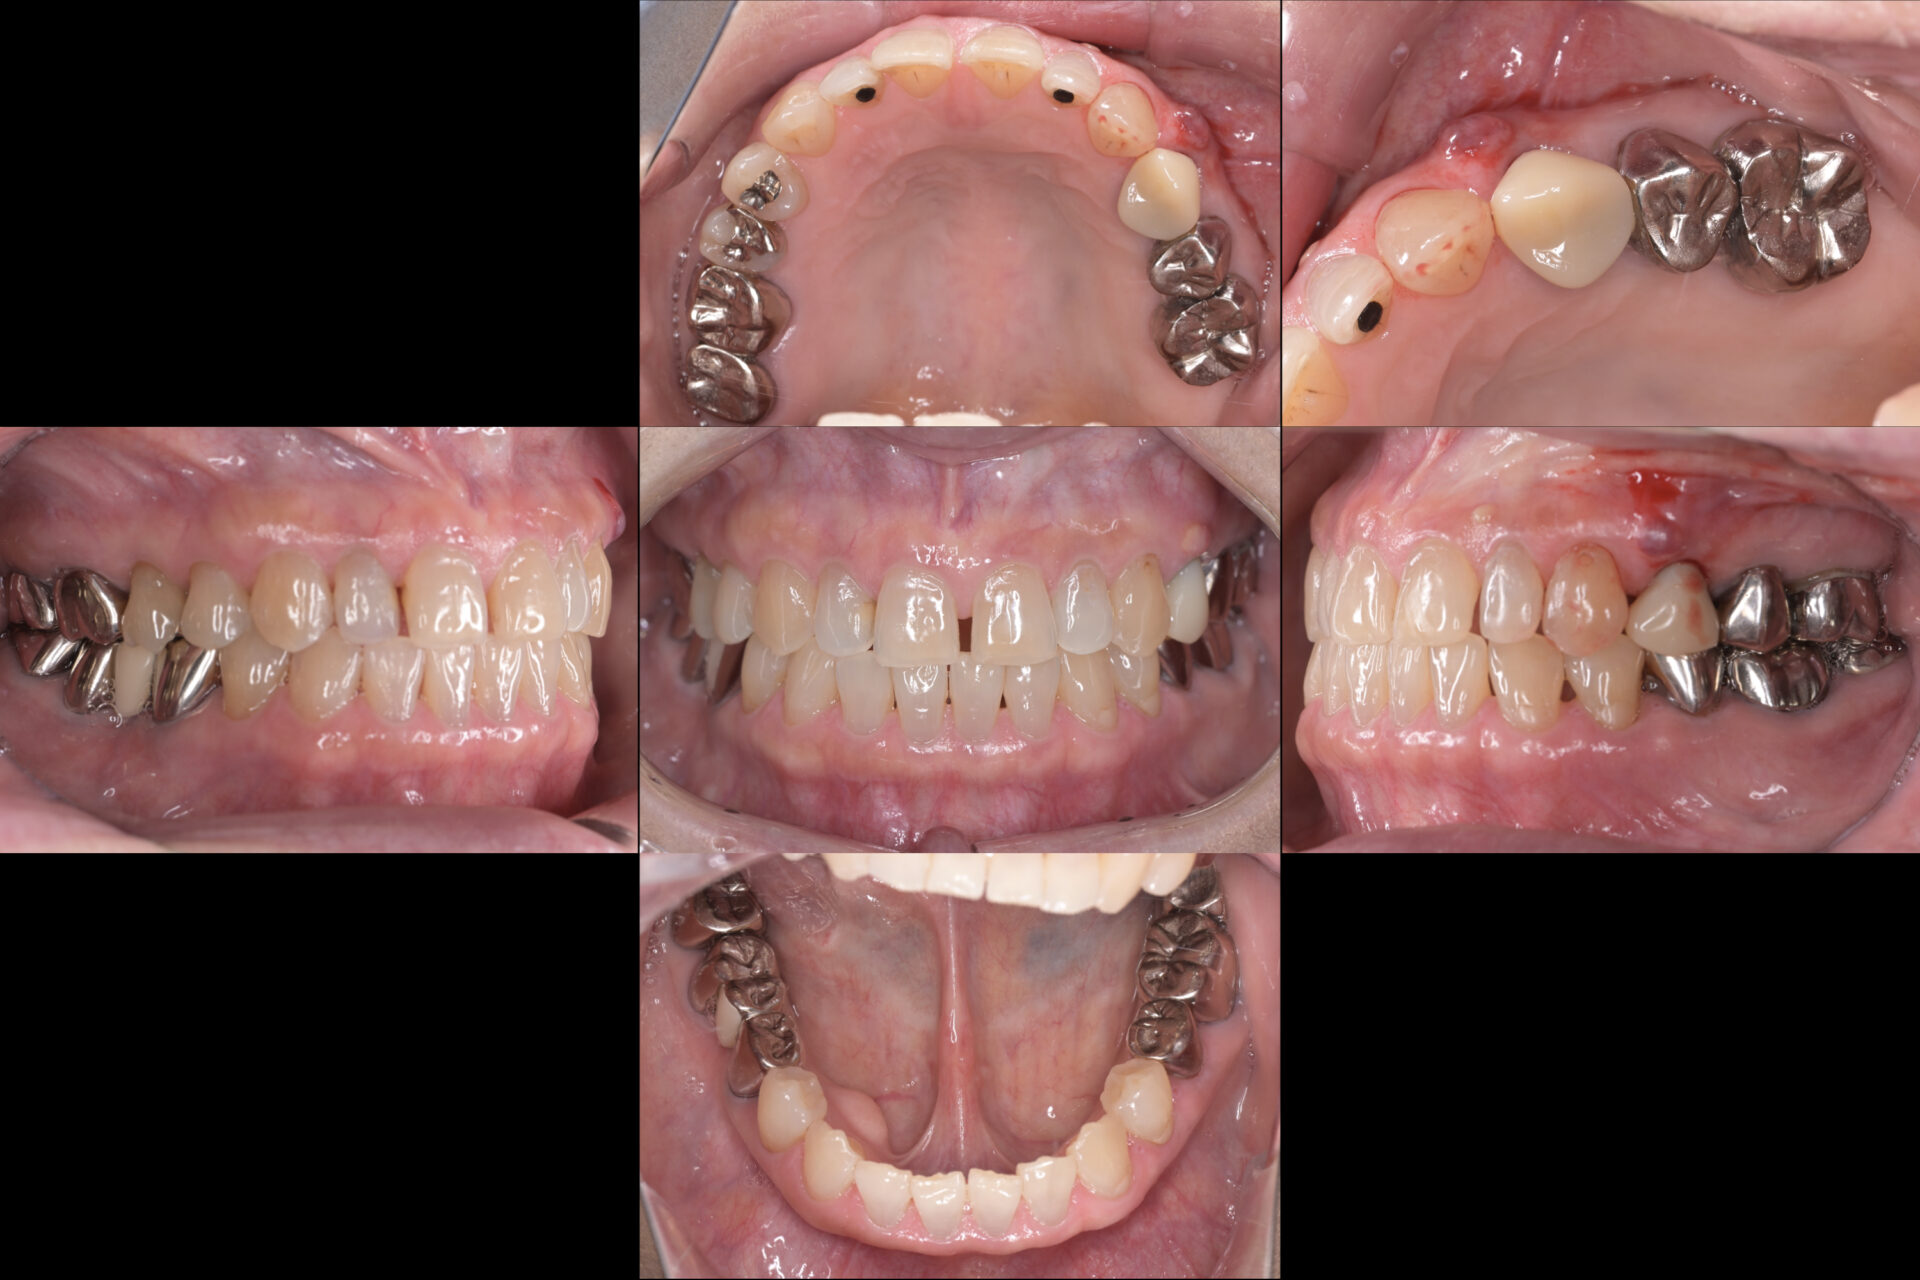

初診時と治療終了後

初診時

以前より腫れが大きくなったり小さくなったりしていて様子を見ていたが、最近腫れが大きいまま消えないことから受診されました。

歯根の破折を疑い、歯周検査(歯茎の状態確認)やCT撮影を行ったところ割れていることが判明したため、残念ながら抜歯を行うことになりました。